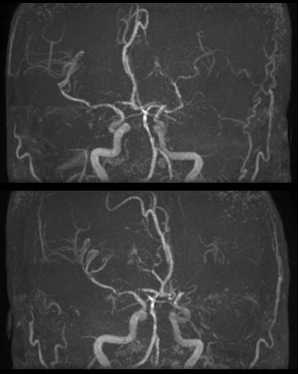

导丝怎么扩【载药时代 球扩天下】NOVA DES®颅内药物洗脱支架在颅内富穿支区域使用体会二例!_https://www.jmylbn.com_新闻资讯_第22张

导丝怎么扩【载药时代 球扩天下】NOVA DES®颅内药物洗脱支架在颅内富穿支区域使用体会二例!_https://www.jmylbn.com_新闻资讯_第23张

影像结论:左侧大脑中动脉完全开通,达3级再通。